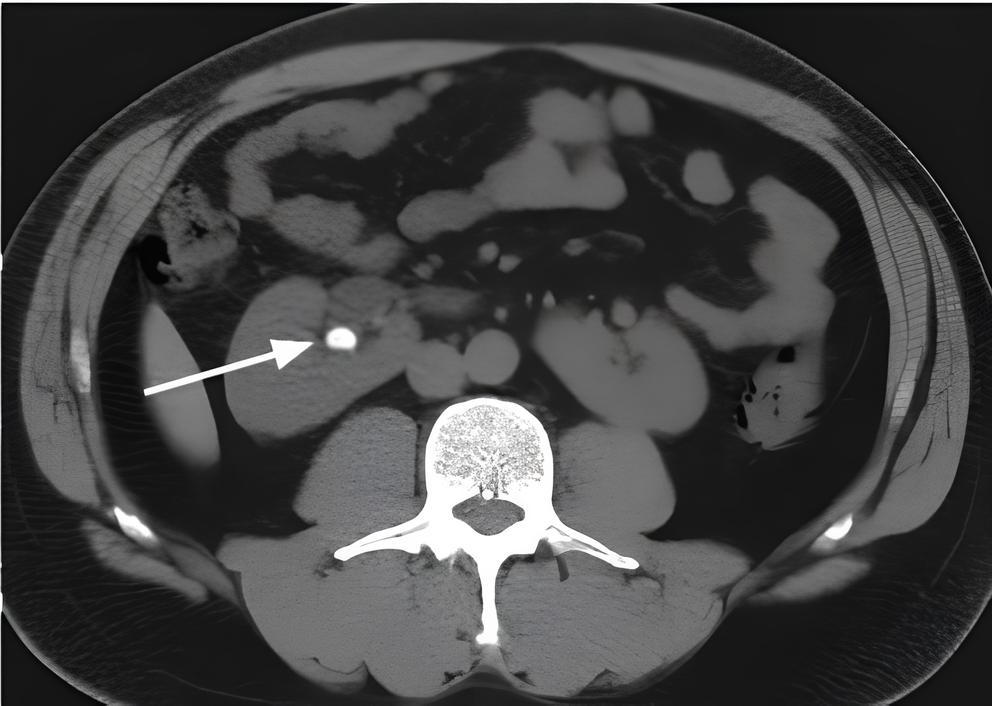

Конкременты почек кт

Конкременты почек кт 104 фотографий